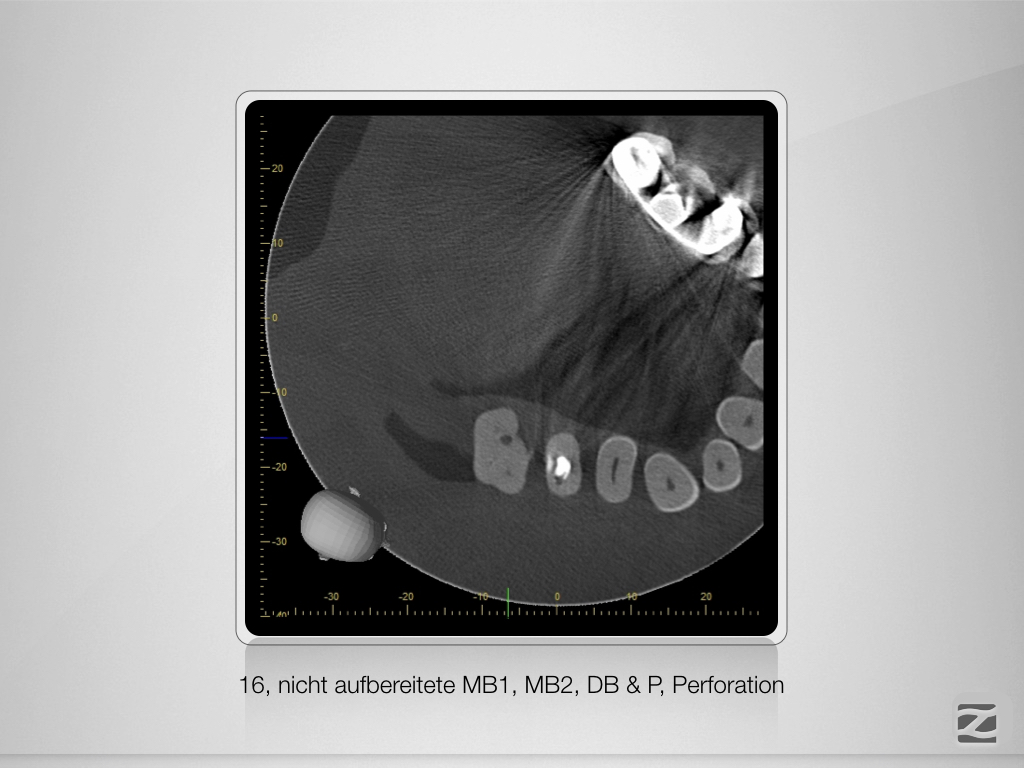

Wie sag‘ ich’s nur dem Kinde?